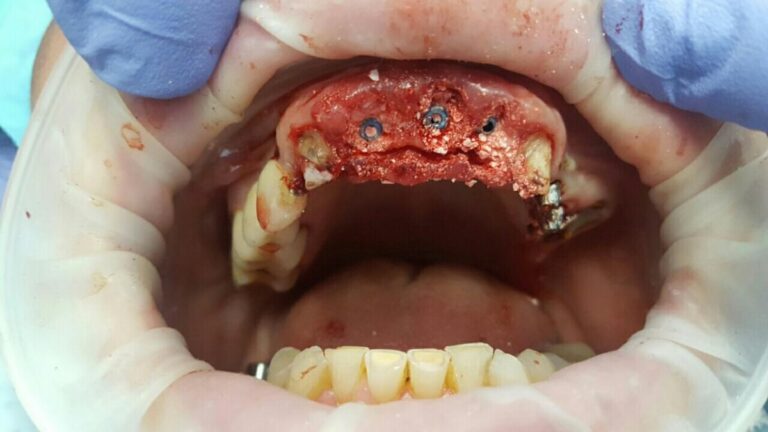

A patient case to the dental clinic with complaint connected with frond teeth defects. After the examination, he decided to provide dental treatment that includes immediate implantation of Alpha Dent implants. During the surgery he has placed 3 Alpha Dent implants in extracted teeth alveolar sockets. Then he placed allomaterial for bone regeneration over implants and sutured the wound.